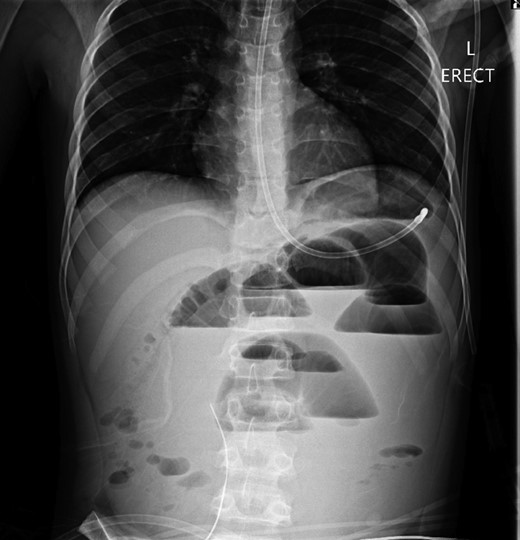

A 10-year-old boy presented unwell with generalized peritonitis after 3 days of abdominal pain, nausea and anorexia. He had a low-grade fever but all other vitals were within normal limits. Blood tests showed a raised white cell count of 16 × 109 with neutrophilia and raised C-Reactive Protein of 127 mg/l. Laparoscopy revealed generalized purulent peritonitis secondary to perforated appendicitis. Appendicectomy was performed and the appendiceal stump was secured. Lavage of the abdomen was performed with a minimum of four litres of warmed normal saline. Fluid was suctioned, an abdominal drain was placed and the pneumoperitoneum was deflated. By the second postoperative day, he developed an ileus with persistent vomiting (Fig. 1). This was managed conservatively with nasogastric intubation, bowel rest, electrolyte replacement and fluid therapy. It became clear by the fifth postoperative day that the patient had intestinal obstruction. On examination, he had a distended abdomen, with intractable nausea and vomiting. Blood tests revealed a normal white cell count and potassium remained at 3.3 despite supplemental intravenous replacement. Abdominal X-ray revealed a small bowel obstruction and he was taken back to theatre for an emergency laparotomy (Figs 2 and 3). A small bowel volvulus was discovered, with no evidence of intestinal malrotation. The volvulus involved a segment of distal jejunum to proximal ileum causing complete small bowel obstruction.

Erect chest radiograph on postoperative day 2 suggestive of small bowel ileus.